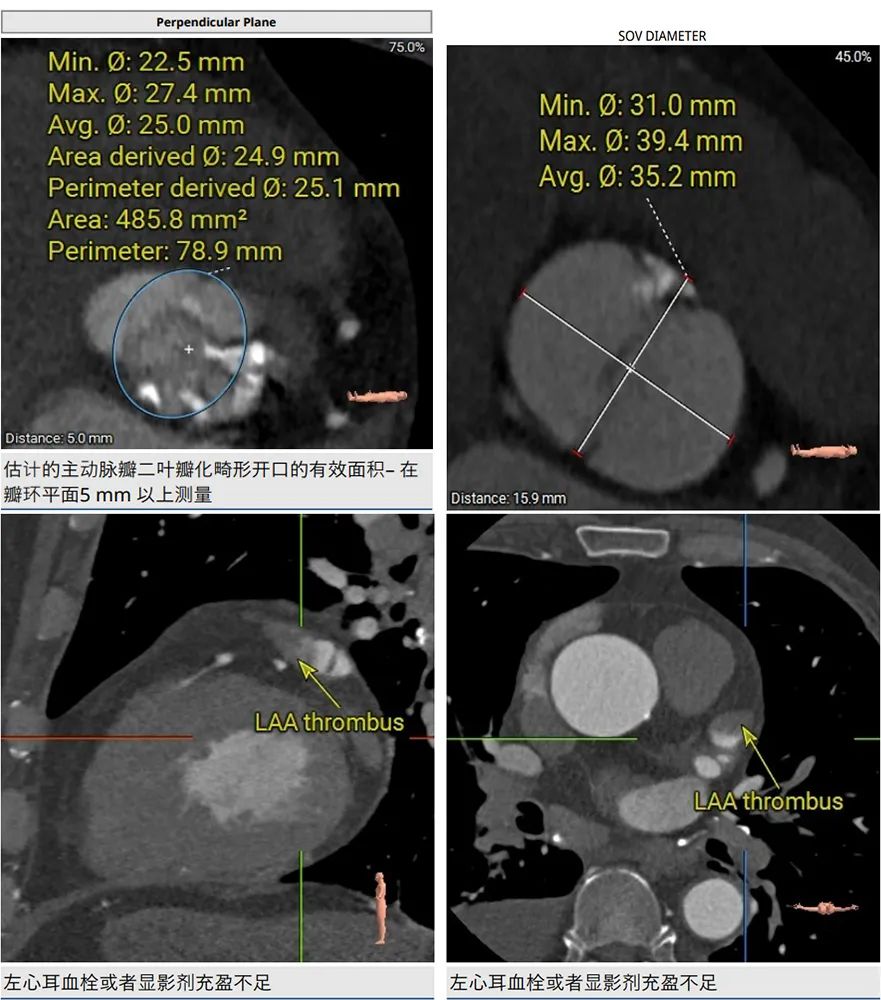

CT分析:

术前CT分析判断该心耳为反鸡翅型左心耳,选择偏下略偏前的位置进行房间隔穿刺。在工作体位造影后,可见左心耳内梳状肌发达,反鸡翅叶显影清晰,鞘管轴向佳。经DSA测量左心耳开口18mm深度17mm,结合TEE测量数据,综合考虑选用WATCHMAN24mm封堵器进行封堵。在展开封堵器时利用在体内借深度技巧,保证封堵器封堵位置合理。封堵器展开后经造影检查封堵器封堵效果理想,牵拉试验稳定。超声评估封堵器各角度无残余分流,位置理想,满足PASS原则,随即释放封堵器,一站式手术顺利结束。